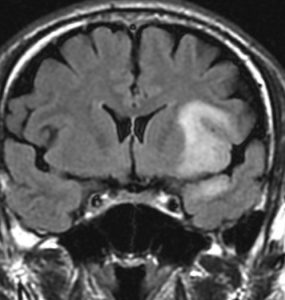

若い女性の左前頭葉から島回,側頭葉を侵す腫瘍で,てんかん発作で発症し,開頭生検 biopsy しました。

一部で,細胞密度が高く,核の腫大とクロマチンの増量,核間距離の短縮があり,核分裂像が認められ,MIB-1染色率が10%です。組織学的には退形成性乏突起膠腫グレード3とされました。

IDH変異あり,1P/19q欠失あり,ATRX変異なしです。

乏突起膠細胞系グリオーマなので,放射線治療の高線量領域はあまり広くとりません。

IMRT Simultaneous Integrated Boost (SIB)で,FLAIR高信号の領域に54グレイ27分割,周囲仮定浸潤領域 generous local areaに46グレイを照射しました。

テモゾロマイド75mg/m2を併用しています。

左の画像は放射線治療直後のMRIですが,すでに腫瘍の縮小がみられます。

テモゾロマイドの維持療法は,24コース 2年間行い,それ以降は無治療としました。

照射後7年の画像です。腫瘍は縮小したまま,患者さんは無症状で経過しています。